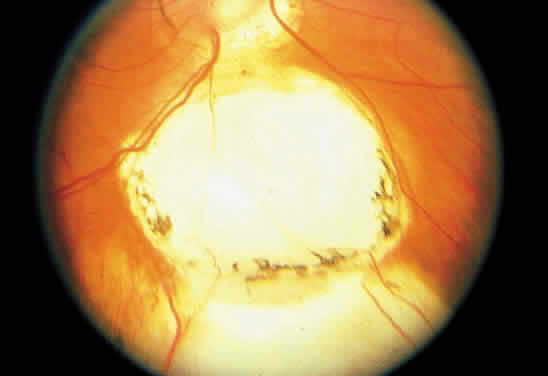

Leber's congenital amaurosis accounts for about 10% of congenital blindness and at least 5% of all inherited retinal dystrophies.202,203 The fundi may be normal in this bilateral disease, but when they are abnormal, they include diffuse pigmentary stippling, pale optic nerves, or both (Fig. 25A through C). Blond fundi also may be seen. Other ocular associations may include cataracts, nystagmus, and hyperopia.204,205

Fig. 25. A. Fundus of a 4-year-old child with Leber's congenital amaurosis. Diffuse pigmentary changes are present in the macula, the optic disc is slightly pale, and the retinal arteries are somewhat narrowed. The child has nystagmus, and there was no central fixation in either eye. B. Fluorescein angiogram of A reveals a pattern of mottled hyperfluorescence better delineating the posterior-pole retinal pigment epithelium disturbance. C. Peripheral fundus photograph shows more marked pigmentary changes. D. The electroretinogram is flat in each eye. (Courtesy of Dr. William Tasman)

The children are usually blind, typically with visual acuity ranging from 20/200 (6/60) to hand motions, or become so during the first year of life. Severe night blindness, and occasionally photoaversion, also is present.206 Roving eye movements may be apparent because of the poor visual acuity.

The electroretinogram is crucial for making the diagnosis and is either flat or shows only minimal responses (see Fig. 25D). This disease is autosomal recessive, and it may represent a type of retinitis pigmentosa, since children with a progressive form may develop fundi identical to the typical retinitis pigmentosa fundus by the middle childhood years.205,207 It is thought that the impaired development or extremely early degeneration of photoreceptors is related to a mutation on chromosome 17, which causes impaired production of a retinal guanylate cyclase.203,208,209